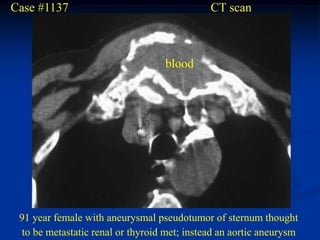

Case #1137                                   CT scan

blood

91 year female with aneurysmal pseudotumor of sternum thought

to be metastatic renal or thyroid met; instead an aortic aneurysm